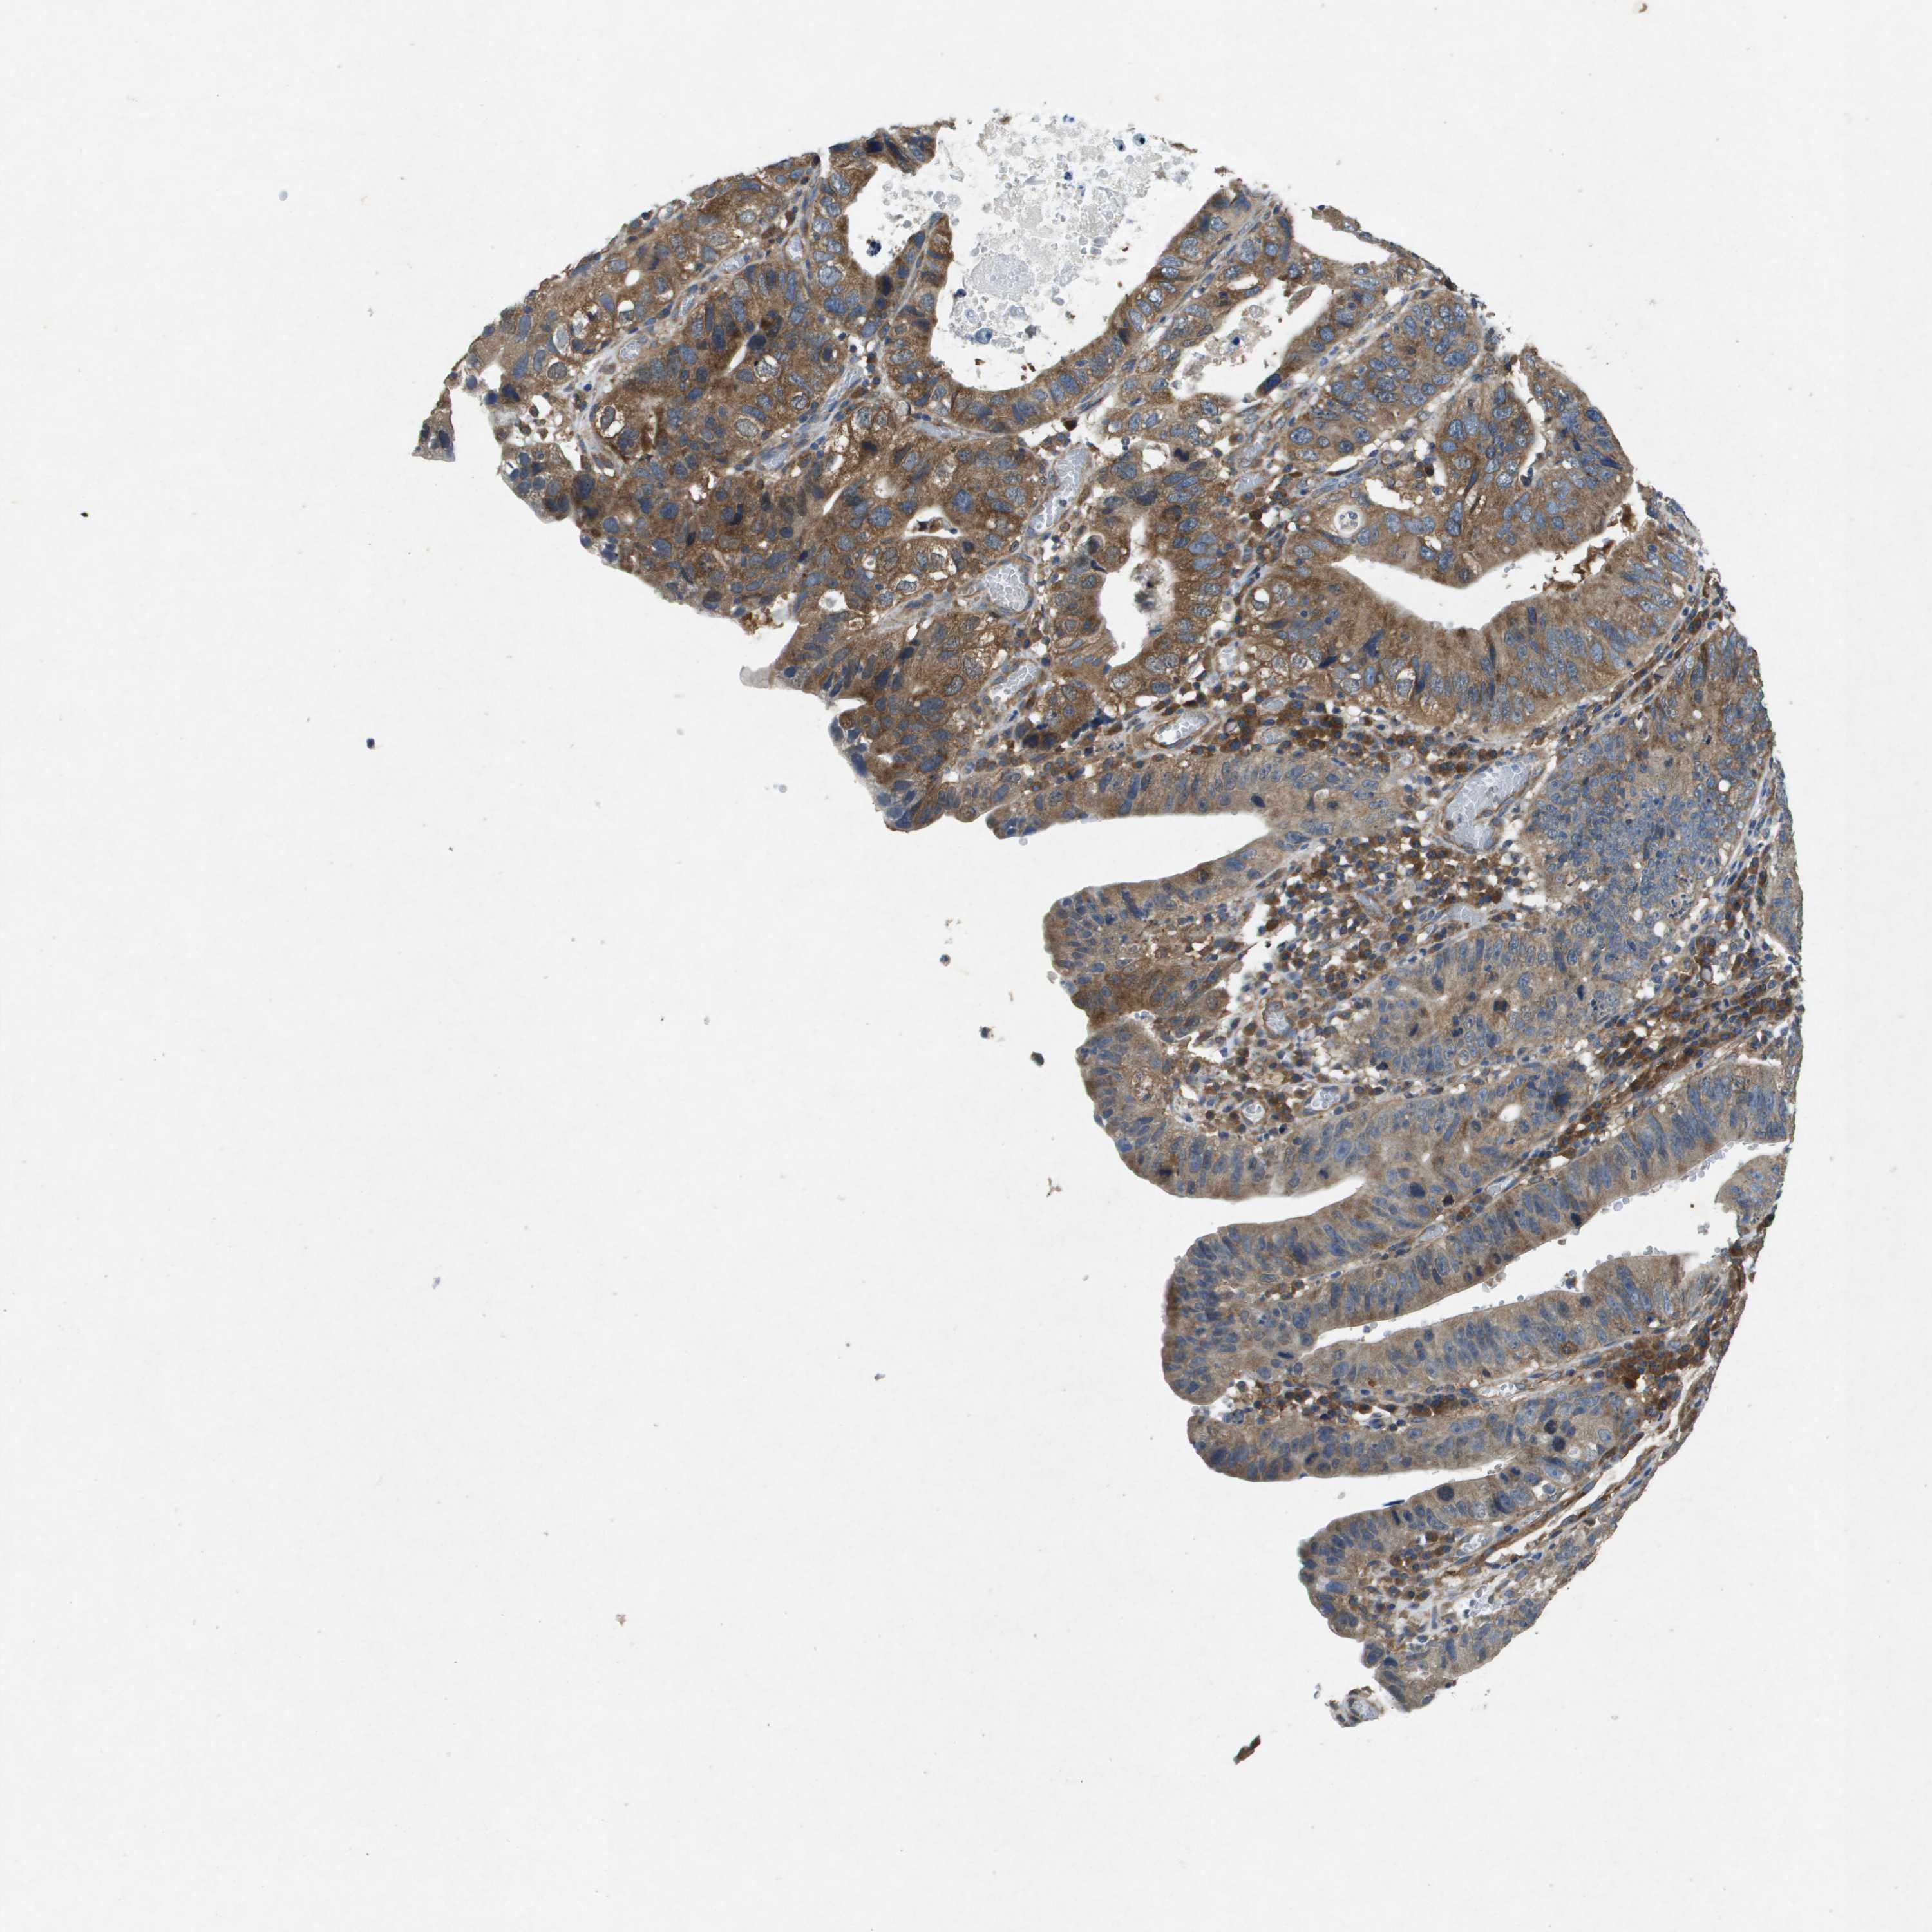

STOMACH CANCER - Protein expressioni

A mouse-over function shows sample information and annotation data. Click on an image to view it in a full screen mode. Samples can be filtered based on level of antibody staining by selecting one or several of the following categories: high, medium, low and not detected. The assay and annotation is described here.

Note that samples used for immunohistochemistry by the Human Protein Atlas do not correspond to samples in the TCGA dataset.

Antibody stainingi

Antibody staining in the annotated cell types in the current human tissue is reported as not detected, low, medium, or high, based on conventional immunohistochemistry profiling in selected tissues. This score is based on the combination of the staining intensity and fraction of stained cells.

Each image is clickable and will lead to virtual microscopy that enables deeper exploration of all samples and also displays staining intensity scores, fraction scores and subcellular localization as well as patient and tissue information for each sample.

Antibody HPA017336

Antibody CAB069423

Staining

High

Medium

Low

Not detected

Intensity

Strong

Moderate

Weak

Negative

Quantity

>75%

75%-25%

<25%

None

Location

Nuclear

Cytoplasmic/membranous

Cytoplasmic/membranous,nuclear

Adenocarcinoma, NOS